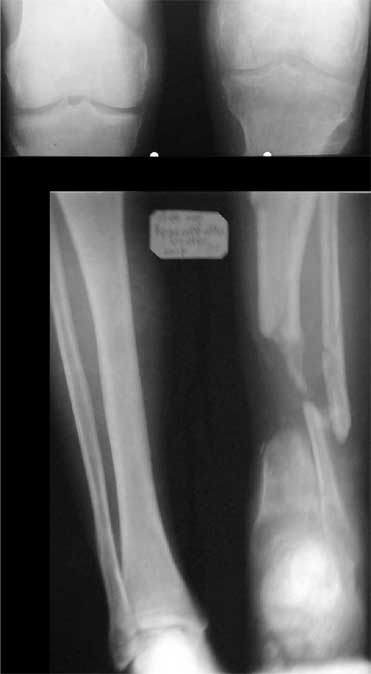

В приложении - моё наблюдение (возможно, уже представлял, тогда

извините).

Нога попала в пресс.

Ко мне больной попал черз 1,5-2 года после травмы и нескольких

операций с синегнойной инфекцией на всю голень. Меня пригласили на консультацию

насчет ампутации.

Лечил я его месяцев 8.

Малоберцовка полностью перестроилась, нога опороспособна.

При ходьбе на дальние расстояния пользуется тростью.

Осталась трофическая язва, периодически закрывается.